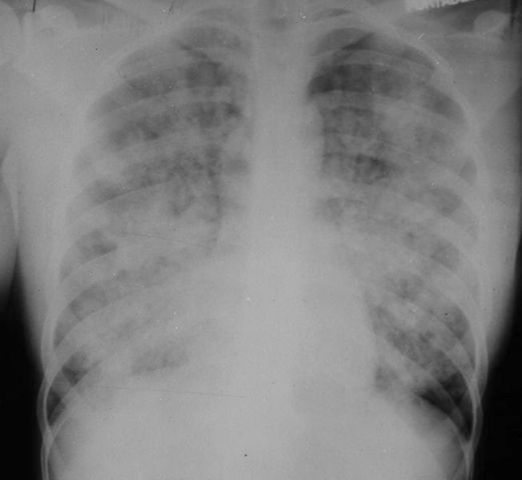

an overview of the history, clinical features, pathology, epidemiology, and first treatments of ARDS